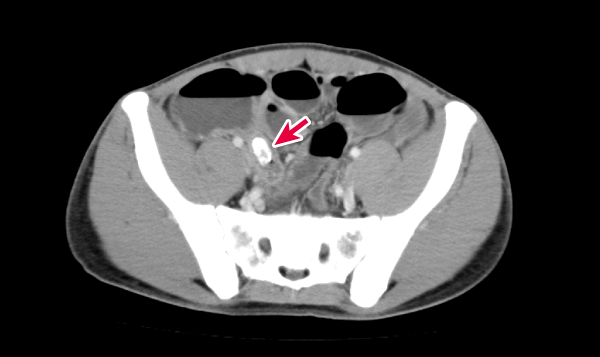

図4 症例1(Aさん)の腹部造影CT

矢印(→)部位に腫大した虫垂と糞石を認める